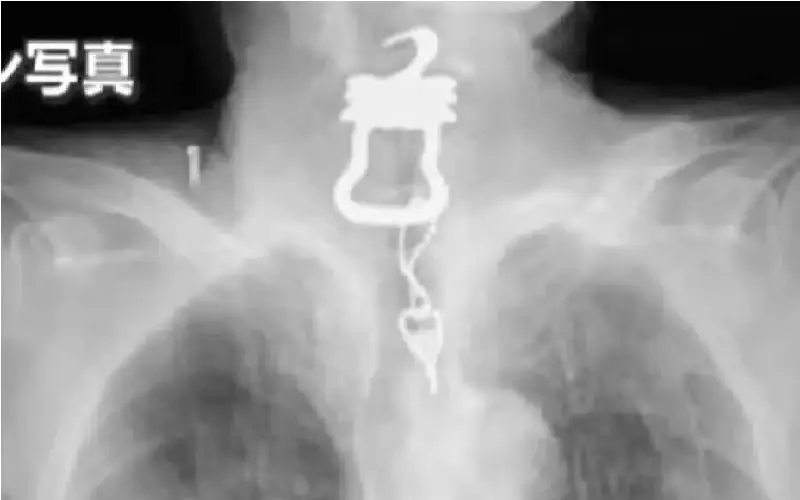

بجرعات زائدة .. ممرض ألماني قتل مرضاه لكي لا يزعجوه ليلا!